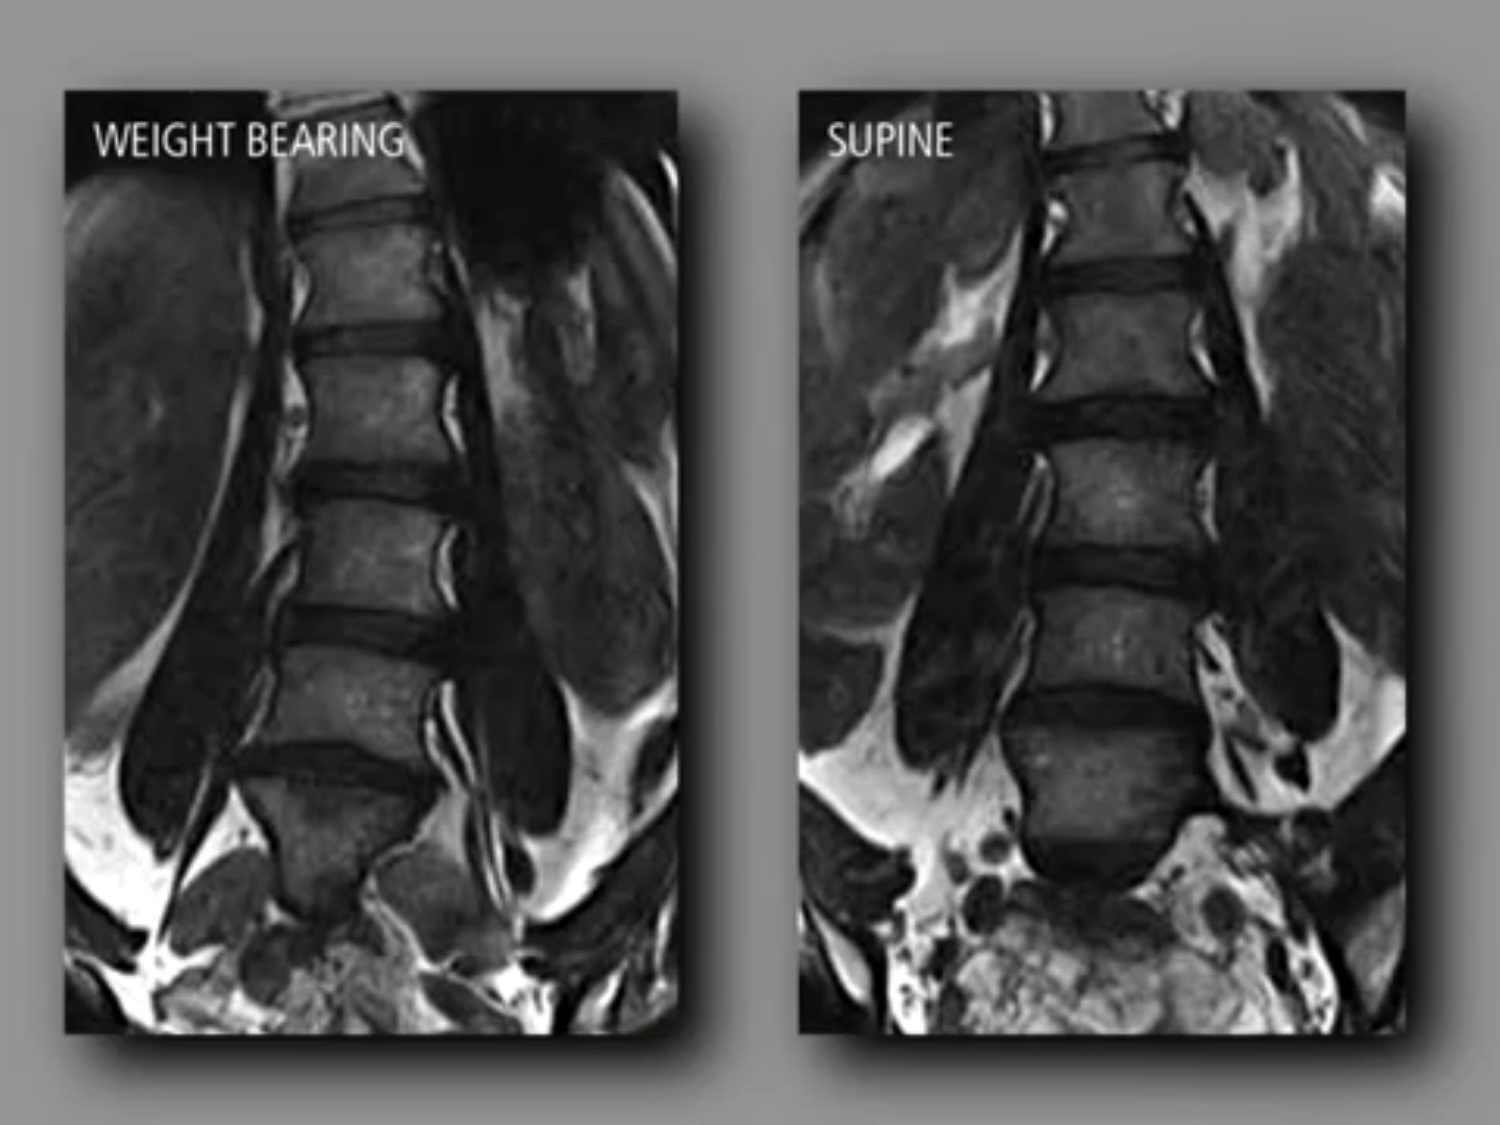

Unique Weight-bearing MRI Capabilities

Weight-bearing studies are easy to perform, allowing patients to be images in the position in which they experience symptoms and providing documentation that can be critical in pre-surgical workflow.